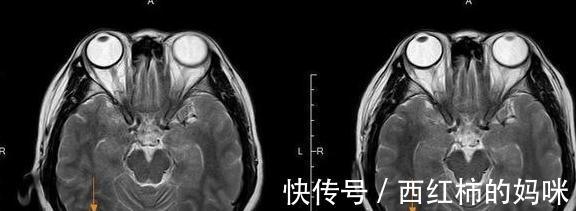

这位患者也是一名女性患者,2015年7月,患者因活动后胸闷气急,咳嗽咳痰增多,在当地医院做了中腹部、颈部CT后发现双侧颈部及颌下多发淋巴结,肝内、双肺多发小结影,通过颈部淋巴结穿刺提示:转移性肿瘤。后来经过证实,诊断为:肺癌伴全身多处转移,同时有脑转移。在诊断结果出来后,医生给出的答案是:肺癌多发脑转移的平均生存期只有3个月左右。得知噩耗后病人以及家属陷入了绝望,不过同样在短暂的绝望后,病人和家属觉得乐观积极认真的治疗来看,万一有奇迹呢?我院的肿瘤科医生根据患者的病史检查结果详细介绍了化疗+靶向治疗方案配合中医药治疗后,患者决定接受治疗。而经过了多个周期的治疗,我们惊喜地发现,病人颅内转移瘤及双肺多发结节都有缩小,病人也很稳定的出院了。

文章插图

左:2015年8月治疗前;右:2015年11月治疗后